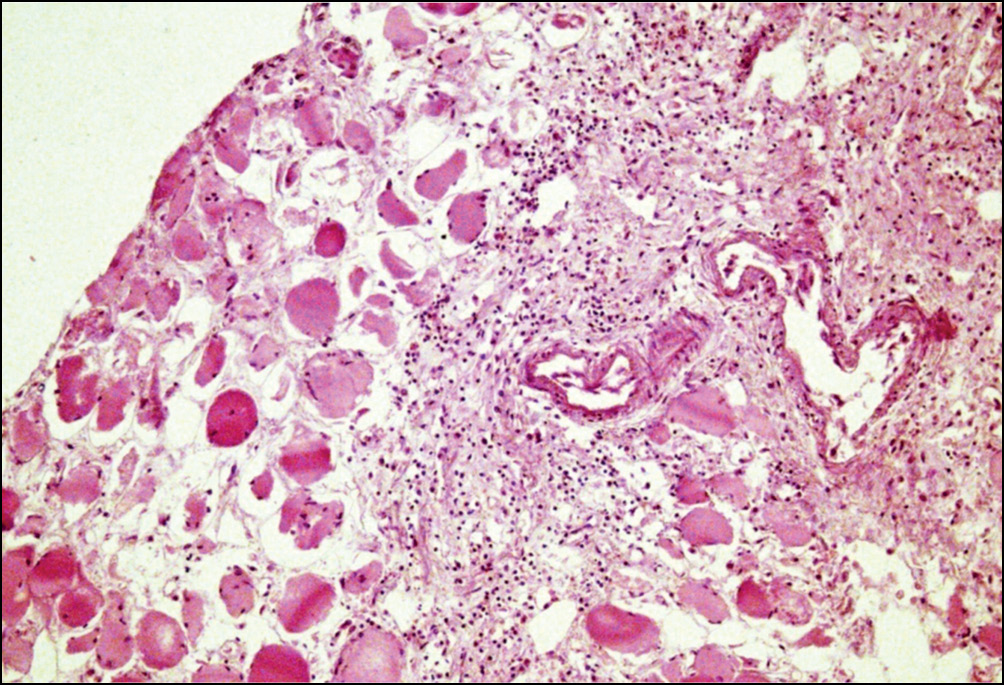

В мышечной ткани наблюдались явления выраженного межуточного отека, участки фиброза с неравномерной лимфоцитарной инфильтрацией с примесью гистиоцитов и лейкоцитов. Отмечались также явления фиброза и фибриноидного набухания стенки сосудов, а также выраженных дистрофических изменений и набухания мышечных клеток (рис. 7).

Рис. 7. Реактивные изменения мягких тканей в зоне перипротезных переломов бедренной кости. В толще мышечной ткани: выраженный межуточный отек, участки фиброза с неравномерной лимфоцитарной инфильтрацией с примесью гистиоцитов и лейкоцитов. Окраска гематоксилином и эозином. Увел. ×100

Fig. 7. Reparative changes in periprosthetic fractures bone tissue of the femoral component. In muscle tissues: pronounced interstitial edema, areas of fibrosis with uneven lymphocytic infiltration mixed with histiocytes and leukocytes. Staining with hematoxylin and eosin. Magnification × 100